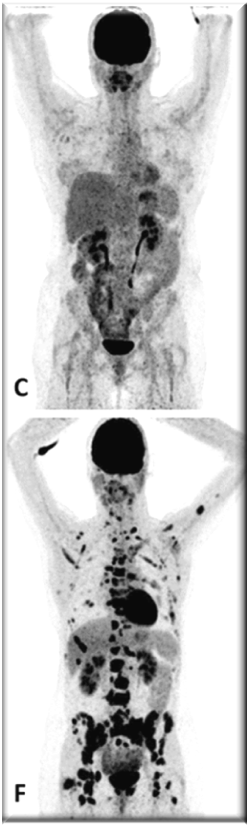

PET images of two patients with metastatic invasive lobular carcinoma responding (A-C) and not responding (D-F) to palbociclib + letrozole

Adapted with permission from Boers, J., et al. European Journal of Cancer. 2020; 126: 11-20

Upper row responder: (A) Baseline [18F]FDG-PET shows pathological uptake in axillary lymph nodes (right side) and in nearly all vertebrae and pelvic bones. (B) Baseline [18F]FES-PET with pathological ER expression in the axial skeleton (vertebrae, pelvic bones, proximal humeri and femora) and in axillar lymph nodes. (C) [18F]FDG-PET after 8 weeks shows almost complete metabolic response. The patient has been on treatment for more than 70 weeks.

Lower row non-responder: (D) Baseline [18F]FDG-PET shows pathological uptake in multiple skeletal lesions. (E) Baseline [18F]FES-PET with only some increased ER expression in thoracic vertebrae. (F) [18F]FDG-PET after 8 weeks shows no metabolic response, with some increase in the pathologic uptake in the multiple skeletal lesions.